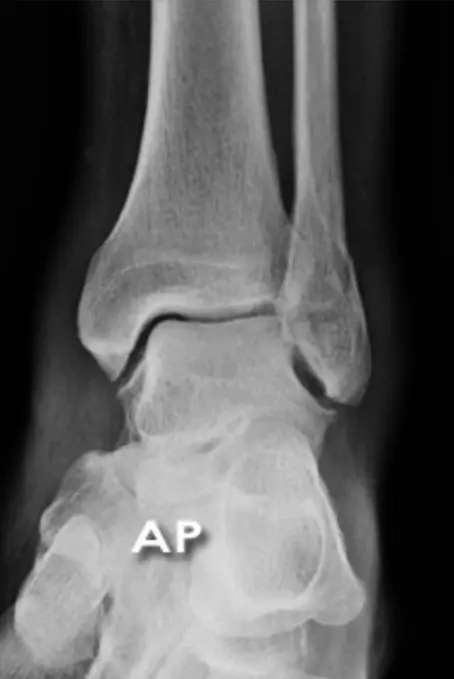

Patient: 32âyearâold male with a severe twisting ankle injury â painful, swollen and unable to stand.

Findings

- Site: lateral malleolus

- Fracture type: simple

- Fracture line: spiral

- Displacement: gap medially

- Special issue: possible ruptured deltoid ligament

Site: Medial malleolus

Type: Simple intraâarticular fracture

Fracture line: Vertical

Displacements

- Gap in joint line

Special issues

- Requires anatomical reduction and absolute stability

- Possible lateral collateral ligament injury